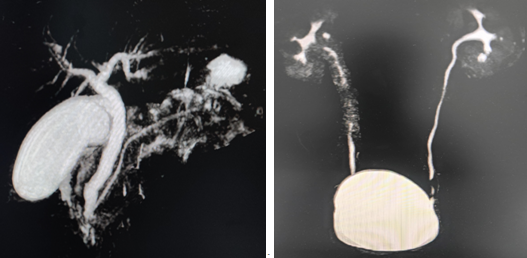

可以采用注射造影剂血管成像,也可以通过TOF,PC,TRANCE等方法进行无造影剂血管成像,无骨伪影,图像清晰,身体各部位血管均可成像,如头颈部动脉造影、下肢动脉造影、肾动脉造影等。

髂血管磁共振成像(CE-MRA) 肾动脉磁共振成像

双下肢磁共振动脉成像 双下肢磁共振静脉成像 头颈部动脉磁共振成像